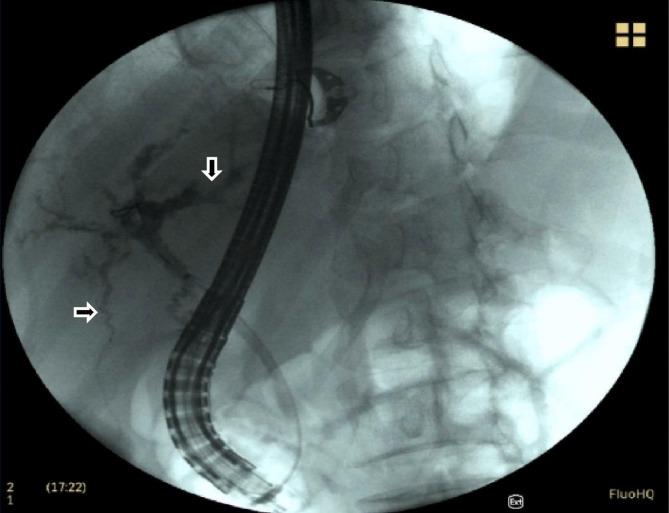

COVID-19 was first recognized by the World Health Organization (WHO) in December 2019 and declared a global pandemic in March 2020. Although COVID-19 primarily results in pulmonary symptoms, it is becoming apparent that it can lead to multisystemic manifestations. Liver damage with elevated AST and ALT is seen in patients with COVID-19. Although the etiology of liver damage is still debated, biliary damage is rarely seen. This case demonstrates a potential complication of COVID-19 in a previously healthy patient. The patient contracted COVID-19 in March 2020 and endured a complicated course including intubation, multiple readmissions, and chronic abdominal pain. He is now awaiting a liver transplant. Our case portrays biliary damage as an additional possible complication of COVID-19 and the importance of imaging in its diagnosis.

新型冠状病毒肺炎(COVID-19)于 2019 年 12 月被世界卫生组织(WHO)首次确认,并于 2020 年 3 月宣布为全球大流行。尽管 COVID-19 主要表现为肺部症状,但越来越明显的是,它可能导致多系统表现。COVID-19 患者会出现 AST 和 ALT 升高的肝损伤。尽管肝损伤的病因仍存在争议,但很少见到胆道损伤。本病例展示了一例既往健康患者 COVID-19 的潜在并发症。该患者于 2020 年 3 月感染 COVID-19,经历了包括插管、多次再次入院和慢性腹痛在内的复杂病程。他目前正在等待肝移植。我们的病例表明,胆道损伤是 COVID-19 的另一种可能并发症,影像学检查对其诊断具有重要意义。